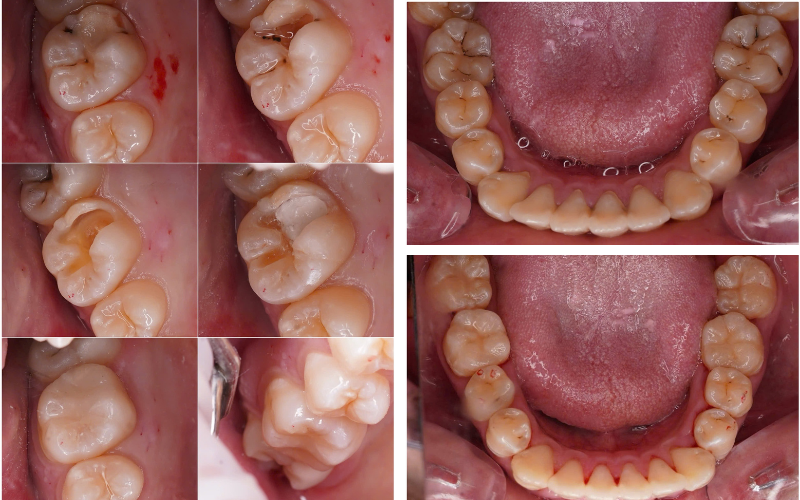

ca điều trị sâu răng

5.1. Điều trị tủy răng (nội nha)

Giải pháp ưu tiên nhằm bảo tồn răng thật.

5.2. Bọc răng sứ sau điều trị tủy

Giúp bảo vệ răng đã mất tủy khỏi gãy vỡ.